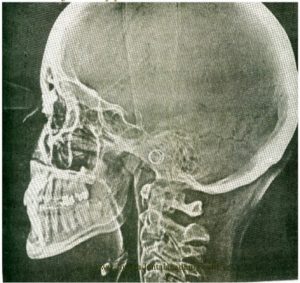

Электрорентгенография (ксерорадиография) — дополнительный метод диагностики в ортодонтии. Его сущность заключается в том, что под воздействием рентгеновских лучей, прошедших через объект исследования, последний экспонируется на предварительно заряженную пластину, в которой имеется полупроводниковый слой (аморфный селен). Электризация пластины осуществляется в специальном зарядном устройстве, после чего она становится светочувствительной. Под воздействием рентгеновского излучения экспонированные участки селена проводят заряд, ранее удерживавшийся на их поверхности. На селеновом слое остается скрытое электростатическое отображение объекта исследования. После проявления изображения его переводят на обычную писчую бумагу и закрепляют парами ацетона. Съемку производят с помощью дентальной рентгеновской установки и электрорентгенографического аппарата ЭРГА-м. Получение и обработка электрорентгенограммы продолжаются около 3 мин, при этом не требуется затемненная лаборатория, а также дорогостоящая рентгеновская пленка, содержащая серебро. Применение данного метода особенно эффективно в ортодонтии, так как на телерентгенограмме, полученной на бумаге, значительно облегчается маркировка антропометрических точек, нанесение линий, дуг, цветного чертежа и последующее измерение угловых и линейных величин.